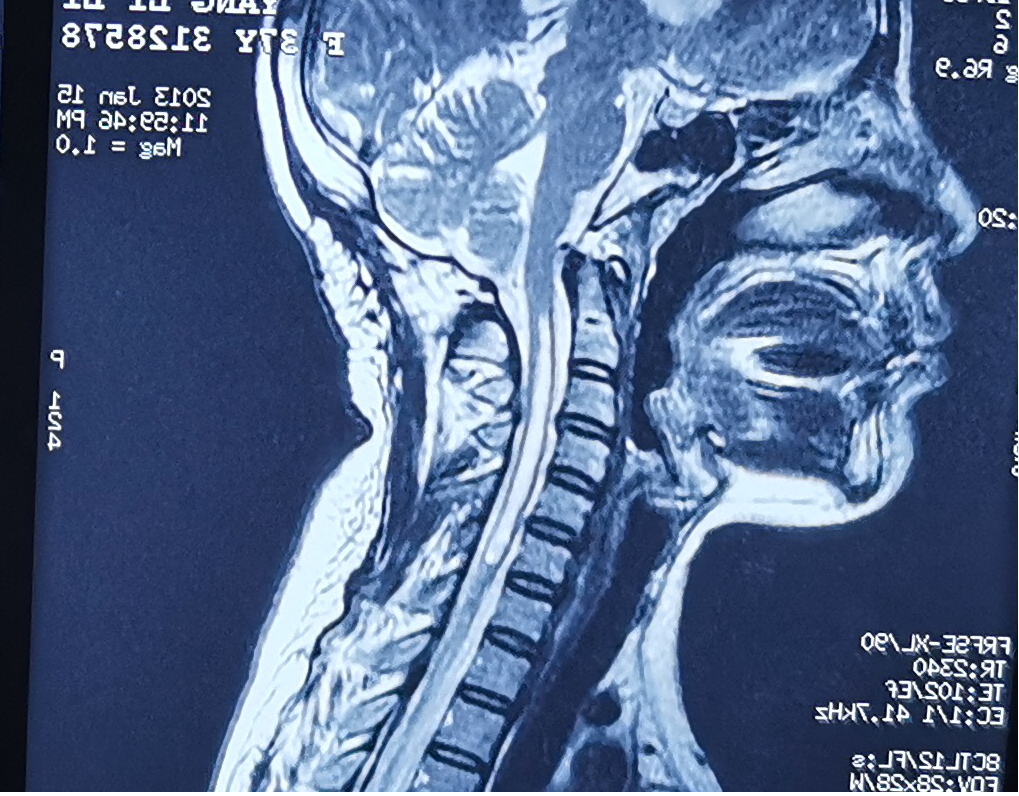

术前患者存在颈椎脊髓空洞症

患者女,44岁,患者于入院前1月余出现右肩部间断疼痛不适,伴活动受限,偶有上肢皮肤麻木,局部皮肤完整,无擦伤及活动性出血,无肿胀,青紫及瘀斑,就诊于当地医院行肩关节影像检查示:右侧肱骨头坏死改变,右侧肩关节结构紊乱,正常结构消失,肱骨头缺血坏死样改变。

当地医院建议转上级医院治疗,患者以“夏科氏肩关节病”收住科室。患者存在脊髓空洞症,右肩受累关节端硬化更明显,伴骨质增生、破坏、骨膜反应、关节脱位、关节面破坏、塌陷,关节脱位,关节周围软组织肿胀,软组织内不规则钙化斑或碎骨片。关节周围肩袖松弛缺失。